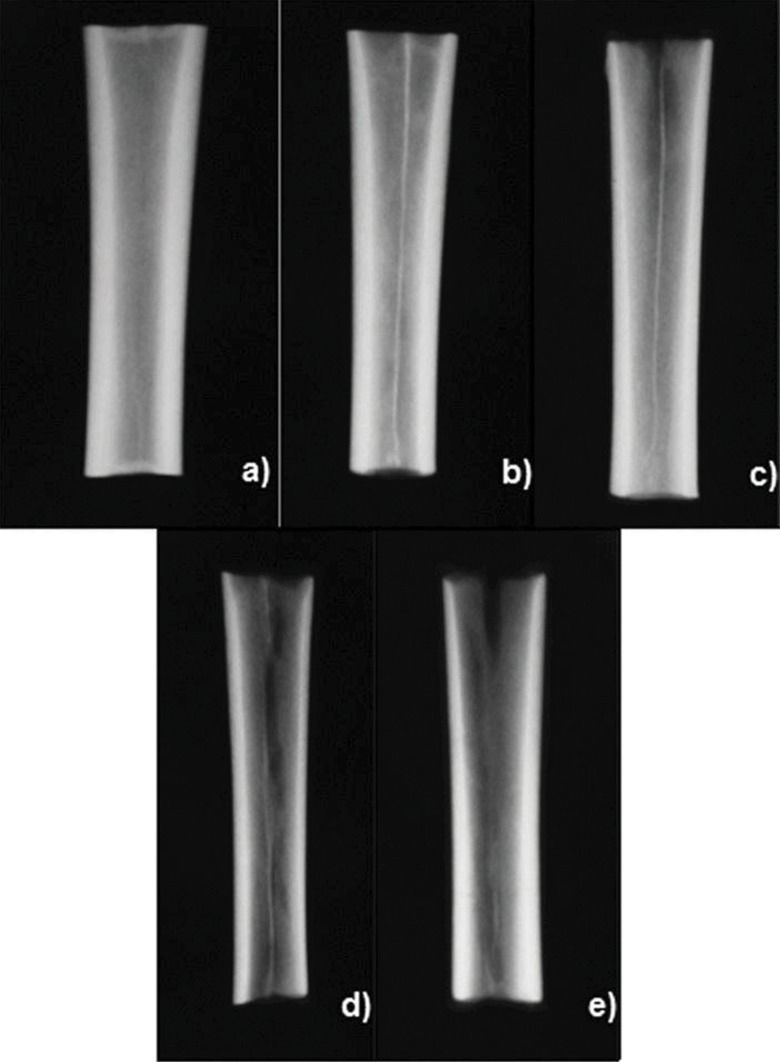

All bones were completely freed from any soft tissue, including the periosteum, by careful dissection and stripping, and divided into three segments of equal length (∼5 cm). Only the middle segment was used for the analyses because we were particularly interested in cortical bone (Figure 1). The bone segments were initially identified, weighed, radiographed and divided into four groups (G6, G12, G24 and G36) of 15 specimens each according to demineralization time. They were then submitted to pre-demineralization UV and BMD analyses, and all parts were thereafter decalcified. Conventional radiographs were recorded and UV and BMD measurements were repeated after demineralization and pre- and post-demineralization images and figures were compared.

Bone demineralization procedureThe bone segments were individually measured for volume via water column dislocation 19 and then placed in identified glass flasks containing 20 times the segment's volume of an aqueous 0.5 N hydrochloric acid solution. The segments were left to stand for 6, 12, 24 or 36 hours according to the group. After the demineralization period, the bone segments were thoroughly washed with deionized distilled water and again submitted to UV and BMD measurements and radiography (Figure 2).

RESULTSThe radiographic appearance of the specimens did not substantially change with the time of demineralization, but some thinning of the cortical layer, dark spots and areas of more pronounced demineralization were visible (Figure 2).